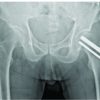

A 40-year-old male, otherwise well, presented with recent onset pain in midfoot region. Physical examination revealed non-palpable mass. No constitutional symptoms of fever or weight loss were present. Hemoglobin was 15 g %, red blood cells 5.15 × 1012/L, total blood count was 9000 × 109/L, and erythrocyte sedimentation rate 10 mm/h. Patient was referred to radiology department for imaging. Radiographs of the foot showed a lytic expansile lesion in first metacarpal with wide zone of transition, no sclerotic margin, and no matrix calcification (Fig. 1).